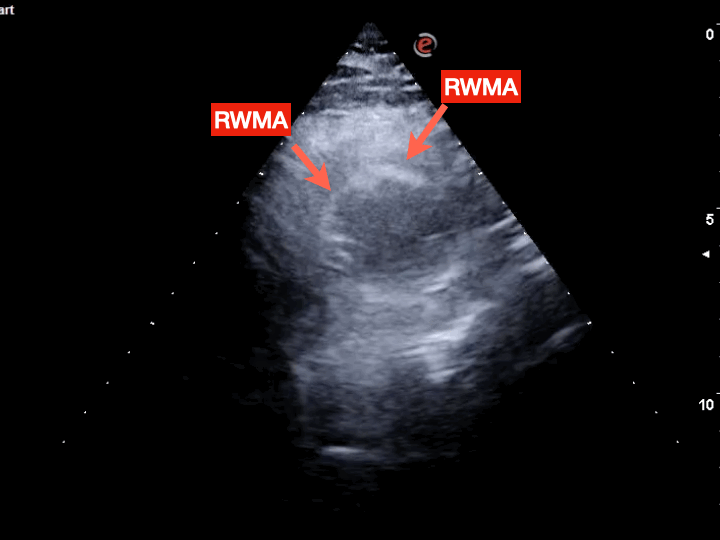

Fig.10是我幫病患掃的echo。很明顯ant./部分septal wall幾乎不動。